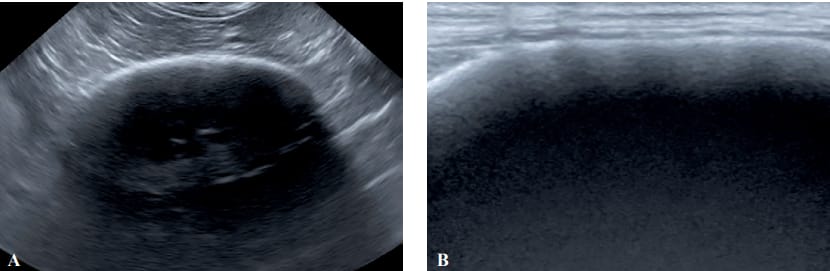

Longitudinal axis image of the left kidney with A. microconvex probe and B. linear probe from dog 2. Note

the severe cortical echogenicity with acoustic shadowing, preventing the evaluation of other renal structures, such as

the parenchyma, medulla or pyelic cavity